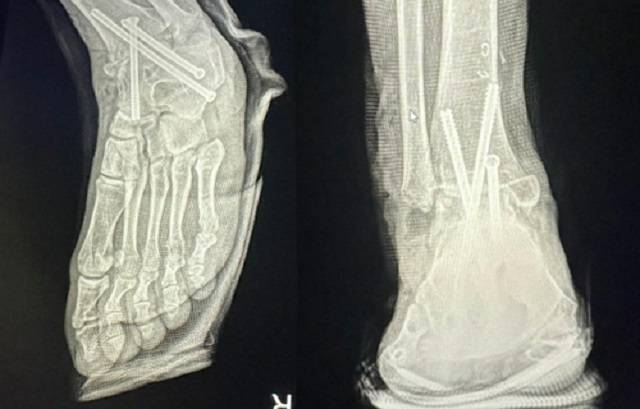

16일 연합뉴스에 따르면 직장인 A씨(29)는 지난 3월 10일 왼쪽 발목이 안쪽으로 접혀 바닥을 제대로 디딜 수 없는 문제를 해결하기 위해 서울의 B 병원에서 수술받았다. 그가 2시간여의 수술 이후 마취에서 깨어나 보니 멀쩡하던 오른 발목뼈가 잘리고 철심 3개가 박혀있었다. A씨는 즉시 경찰에 신고해 의료과실 증거를 확보하고 다시 왼발 수술을 받았다.

B 병원은 A씨의 병원비를 받지 않았고 그의 재활치료를 돕기 위해 병원 근처에 월세방도 얻어줬다. 그러나 A씨의 오른발은 복숭아뼈를 잘라 여러 뼈를 철심으로 연결해 발목이 움직이지 못하도록 고정해 놓았는데, 지금은 뼈들이 다 굳어진 상태여서 과거의 온전한 모습으로 돌아가기 어렵다고 한다.